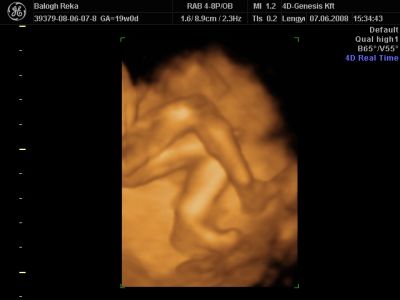

Huhh, hát annyira jó élmény volt, most tök boldog vagyok! Nagyon örülök, hogy mégis elmentem mégegyszer, mert sokat vacilláltam ám. A 4D Genesis egyszerűen szuper, mindenkinek nagyon nagyon tudom ajánlani, ezen belül is engem a Lengyel Györgyné Márti fogadott. Szuper ez a nő, akkora átéléssel és profizmussal csinálta az egész vizsgálatot! Mindent részletesen megnézett, megmutatott, elmagyarázott, nem sajnálta az időt. A felvétel gyönyörű lett, az egész baby nagyon szépen látszik, végig fent volt és mocorgott, hihetetlen aranyos volt, és nagyon szép!

Bemutatott párszor, ezek mind meg is vannak örökítve!

Na és a lényeg...jöjjenek a sztárfotók! Bocsi előre, 8 lesz és kicsit nagyok, de nem tudtam választani, azokat a bemutatásokat mind muszáj volt felraknom, tök vicces!